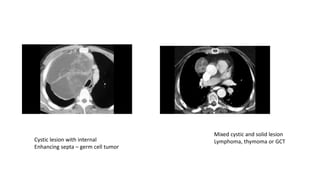

Cystic lesion with internal

Enhancing septa – germ cell tumor

Mixed cystic and solid lesion

Lymphoma, thymoma or GCT